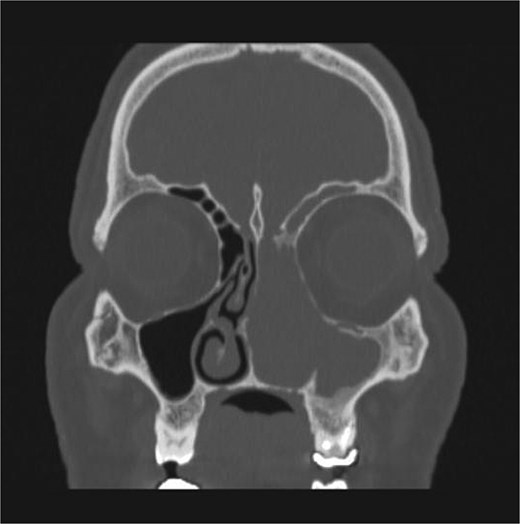

CT showed a heterogeneously enhancing mass completely occluding the left nasal cavity, left ethmoidal, maxillary and frontal sinuses, extending to left pterygopalatine fossa. It is associated with bony erosion of the posterior nasal septum and the left medial maxillary wall (Figs 1 and 2). Findings were suggestive of inverted papilloma vs sinonasal malignancy. Therefore, biopsy was recommended.

Coronal section of CT paranasal sinus with contrast bone window showing the bony erosion in the nasal septum and maxillary sinus wall.